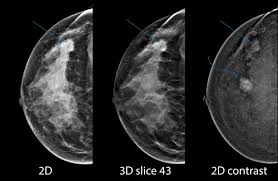

ماموگرافی دیجیتال در بعضی از مراکز رادیولوژی موجود می باشد. ماموگرافی دیجیتال برای خانم های کمتر از ۵۰ سال که بافت پستانی متراکم تری دارند مناسب تر می باشد. در ماموگرافی دیجیتال تصویر در حین انجام ماموگرافی بر روی مانیتور پدیدار می شود که دیگر نیازی نیست پزشک برای مشاهده تصویر صبر بنماید. همچنین ماموگرافی دیجیتال تصویری واضح تر بر روی مانیتور نشان می دهد. انواع ماموگرافی همانند ماموگرافی دیجیتال در موسسه سونوگرافی و رادیولوژی دکتر حسین صدری وجود دارد. دستگاه های موسسه دکتر صدری به روزترین تجهیزات را داراست که با عث می شود کمترین میزان اشعه و کمترین میزان درد را تجربه کنید. همچنین جهت رفاه حال شما عزیزان تکنسین خانم و پزشک خانم نیز در موسسه دکتر صدری حضور دارند. جهت اطلاع از ساعات کاری لطفا با مطب تماس حاصل فرمایید.

عکس ماموگرافی زنان

بعد از انجام ماموگرافی عکس ماموگرافی یا سی دی آن به شما تحویل داده می شود. عکس ماموگرافی بر اساس نوع دستگاه ماموگرافی و نمای تصویر برداری ظاهر متفاوتی دارد. نماهای مختلف ماموگرافی به تشخیص دقیق تر ضایعه کمک می کند. در ادامه چند نوع عکس ماموگرافی را مشاهده می کنید.